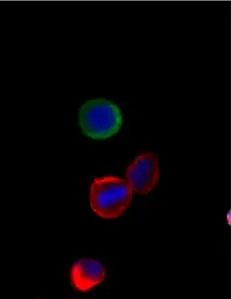

Example images from patient blood samples

Single mesenchymal CTCs - breast

Cluster of EMT CTCs - breast

Examples of Portrait+ CTC staining kit samples